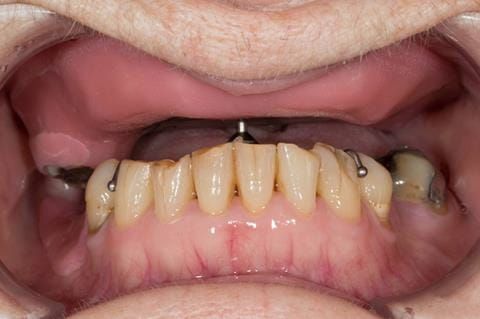

- Eight mandibular anterior teeth worn incisal edges from now extracted maxillary anterior crowns. Gingivitis - owing to inadequate oral hygiene.

Following consultation and second discussion appointment the patient chose to have option 2 namely, a window denture - maxillary cobalt chromium based partial denture. The clinical situation and treatment process is shown in detail below with photographs. The patient was successfully rehabilitated with this and her quality of life considerably improved. The clinical work was provided by Finlay and the technical work by Rowan.